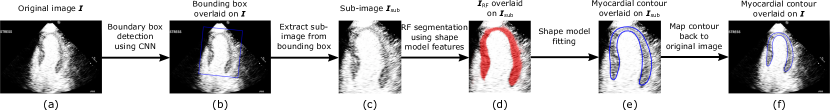

Refer to caption

Figure 1: Overall pipeline of our myocardial segmentation approach. The three main components of the approach are bounding box detection (a-b), RF segmentation (c-d) and shape model fitting (d-e).

In this paper, we propose a fully automatic method that segments the myocardium on 2D MCE image. The method is based on random forest (RF) [7] and incorporates global shape information into the RF framework through the use of a statistical shape model that explicitly captures the myocardial shape. This provides stronger and more meaningful structural constraints that guide the RF segmentation more accurately. Our method takes the advantages of both the RF and the shape model in order to address the above challenges of MCE myocardial segmentation. The RF has strong local discriminative power and serves as a good intensity/appearance model that captures the large intensity variations of the MCE data. The shape model captures the myocardial shape variations of the MCE data and imposes a global shape constraint to guide the RF segmentation. This avoids inaccurate segmentation due to misleading intensity information on the MCE. Fig. 1 shows the overall pipeline of our myocardial segmentation approach. The main contributions of our proposed method are:

• A novel shape model (SM) feature is introduced which incorporates the shape model into the RF framework. The feature improves RF segmentation by generating smoother and more coherent RF probability map that conforms to myocardial structure and shape. (Fig. 1c-d)

• A shape model fitting algorithm is developed to fit the shape model to the RF probability map to produce a smooth and plausible myocardial contour. (Fig. 1d-e)

• A convolutional neural network (CNN) is employed to automatically detect a bounding box enclosing the myocardium. This pre-processing step removes any pose variations of the myocardium and improves the subsequent RF segmentation using SM features. The two-stage process of bounding box detection followed by shape inference is similar to [9]. (Fig. 1a-b)

The overall pipeline for our myocardial segmentation method is summarized in Fig. 1. Given an input MCE image 𝑰𝑰\boldsymbol{I}, a bounding box enclosing the myocardium is first detected using a CNN. Using the bounding box, a sub-image 𝑰subsubscript𝑰sub\boldsymbol{I}_{\textrm{sub}} is cropped out from 𝑰𝑰\boldsymbol{I} and then rescaled to a fixed size. Next, an RF classifier with SM feature is used to predict a myocardial probability map 𝑰RFsubscript𝑰RF\boldsymbol{I}_{\textrm{RF}} of the sub-image. A statistical shape model is then fitted to 𝑰RFsubscript𝑰RF\boldsymbol{I}_{\textrm{RF}} to give a final myocardial contour which is subsequently mapped back to the original image space. For sequence segmentation, an additional constraint term is added to the shape model fitting step to ensure temporal consistency in the segmentations.